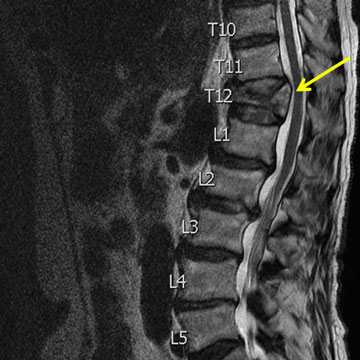

Tuberculosis